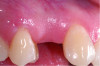

Fig 6 through Fig 8. Example of increasing KMW with an APF at implant uncovery. Fig 6: initial presentation showing lack of KMW; Fig 7: healing abutment placement with APF; Fig 8: 2 months post-treatment. (The dotted lines indicate the MGJ.) Fig 9 through Fig 11. Example of increasing KMW with an APF and FGG at implant uncovery.